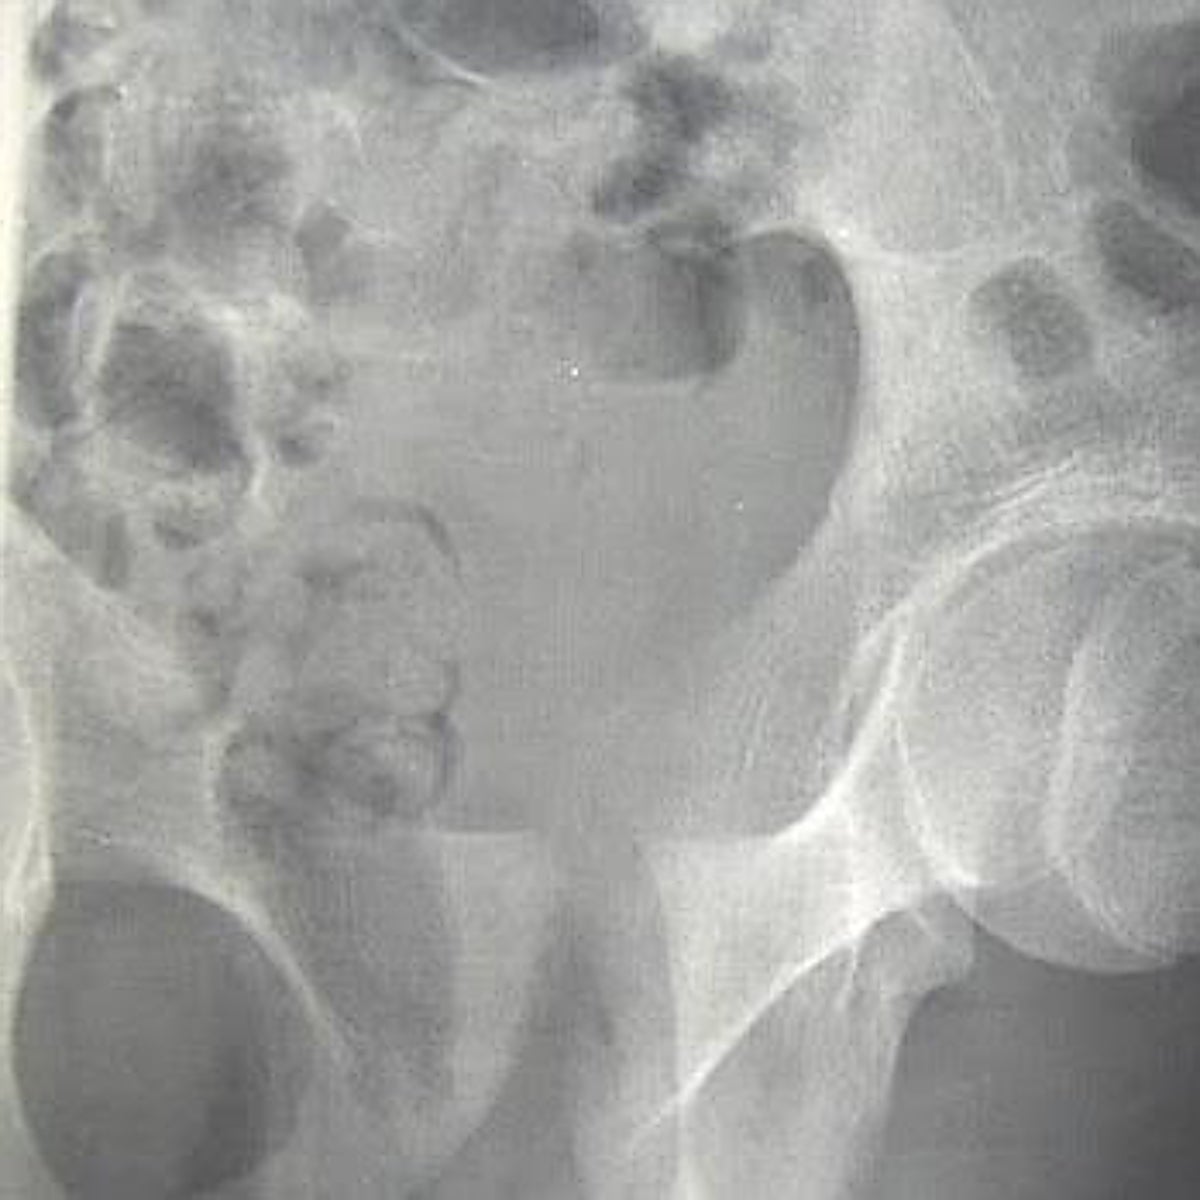

Precisamente, el pasado mes de julio se publicaron en la revista 'New England Journal of Medicine' los resultados de un gran ensayo clínico que no respaldan el uso de suplementos de vitamina D para reducir las fracturas en hombres y mujeres estadounidenses sanos. En comparación con el placebo, la vitamina D3 suplementaria (2000 UI/día) no redujo las fracturas totales, no vertebrales o de cadera. Los análisis también mostraron que no hubo efectos de la vitamina D3 suplementaria en las principales fracturas osteoporóticas, fracturas de muñeca o fracturas pélvicas.

Sí que está avalada la suplementación, explica la experta, en personas diagnosticadas con osteoporosis y riesgo de fracturas para disminuir el riesgo de nuevas fracturas. También en pacientes con determinadas patologías renales o hepáticas que complican la activación de la vitamina D propia o en mayores que viven en residencias y tienen una menor exposición solar; pacientes que toman determinados fármacos que complican la absorción o que se han sometido a una cirugía gástrica.